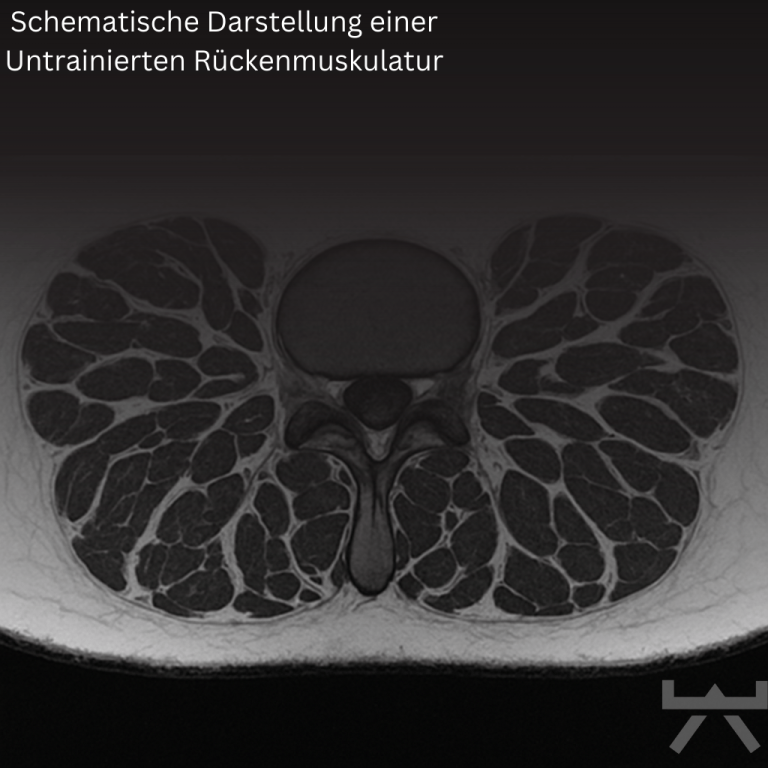

Über die Jahre geht nicht nur Muskelmasse und dementsprechend auch Muskelkraft verloren, sondern auch die Muskellänge. Muskelverlust entsteht – genauso wie der Aufbau von Muskulatur – indem die kleinsten Einheiten der Muskelzellen (= die Sarkomere) aufeinander oder nebeneinander ab- bzw. aufgebaut werden. Genau dann, wenn diese Einheiten nebeneinander abgebaut werden, hat der Muskelverlust einen direkten Einfluss auf die Muskellänge. Hinzu kommt, dass die meisten von uns den Alltag hauptsächlich im Sitzen verbringen. Da wir wissen, dass unsere Muskulatur ein dynamisches Gewebe ist, das sich je nach Funktion und Arbeitslänge verkürzen oder verlängern kann, wird ein sitzender Alltag diesen Prozess der Verkürzung höchstwahrscheinlich nicht gerade positiv beeinflussen.